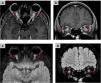

The aim of this work is to provide a diagnostic approach to the potential causes of optic neuropathy, focusing on the radiological findings associated with this pathology. Various etiologies have been identified, including inflammatory and demyelinating optic neuritis, developmental and hereditary diseases, neurodegenerative disorders, infectious conditions, post-traumatic causes, ischemic optic neuropathy (with anterior ischemic optic neuropathy being the most common form), and neoplastic etiologies. Optical coherence tomography and magnetic resonance imaging play a fundamental role in the diagnosis of optic neuropathy, allowing to distinguish patterns of optic nerve involvement. These studies are essential to locate and characterize the different pathologies, increasing the precision of the diagnosis in diseases presenting optic neuropathy as the main symptom. In conclusion, the findings obtained from magnetic resonance imaging are essential in the differential diagnosis of optic nerve diseases, aiding in the localization and characterization of various pathologies affecting either the optic pathway alone or multiple levels of the central nervous system and thereby increasing diagnostic accuracy.